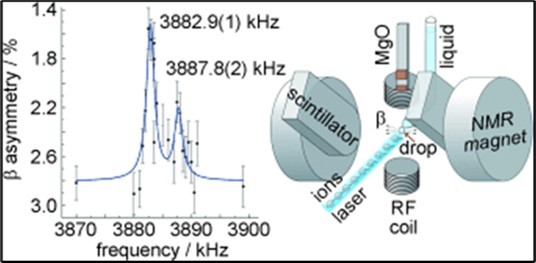

MR spectroscopy analyzes molecules such as hydrogen ions or protons. Proton spectroscopy is more common. There are several metabolites or metabolic products that can be measured to differentiate between tumor types: Lactate or Lac N–acetyl aspartate or NAA Choline or Cho Creatine or Cr Myo–inositol or Myo Glutamate and Glutamine or Glx Lipid. The abundance of these metabolites is measured in units called parts per million (ppm) and plotted as peaks of different heights on the graph. The horizontal axis of the spectrum indicates the amount of chemical shift of each of these materials and the vertical axis indicates the amount of this chemical shift, which is the same signal resulting from the magnetic intensification of the core. By measuring the PPM of each of the mentioned metabolites and comparing them with normal brain tissue, neurologists can determine the type of tissue present. MR spectroscopy can be used to determine the type of tumor and whether it is malignant or benign, etc. Simultaneously with the discovery of MRI, the chemical shift effect was also identified. Chemical shift (chemical shift) is the basis of MRS. The origin of this effect is the response of the electrons of a molecule to the magnetic field 115, 116, 117, 118, 119, 120, 121, 122, 123, 124, 125, 126, 127, 128, 129, 130, 131, 132, 133, 134, 135, 136, 137, 138, 139, 140, 141, 142, 143, 144, 145, 146, 147, 148, 149, 150, 151, 152. In the MRI discussion, the nucleus or proton is affected by an external field with intensity B0 and therefore rotates around the field with the Larmor frequency, but the electrons themselves also create a protective effect or shield around the proton or nucleus, which is called the shielding constant. we say. The greater the electron cloud and the number and characteristics of the electronegativity, the greater this protection is, and therefore the nucleus does not see the actual external value of the field, so we expect hydrogens that are in tissues with less electron shielding to see a greater external magnetic field and according to the Larmor relation They rotate faster around the external field, while for tissues such as fat, where hydrogen protons have stronger bonds with carbons and electron shields, they rotate slower with the Larmor frequency 153, 154, 155, 156, 157, 158, 159, 160, 161, 162, 163, 164, 165, 166, 167, 168, 169, 170, 171, 172, 173, 174, 175, 176, 177, 178, 179, 180, 181, 182, 183. In fact, different metabolites have different hydrogen bonds and considering that the chemical shift in them differs according to what was mentioned, we can use it in Spectroscopy. In general, two different approaches are used in proton spectroscopy: Single voxel method that uses a sequence of STEAM or PRESS pulses and spectroscopic imaging methods that are also known as chemical shift imaging or CSI. In the first attempts to perform spectroscopic imaging, which is also referred to as MRS, the one– dimensional method was performed using phase coding in one direction. By using MRSI coding gradients, the phase methods in two directions were extended to two dimensions and subsequently to three dimensions with three–dimensional coding, which are called chemical shift imaging (Figure 1).